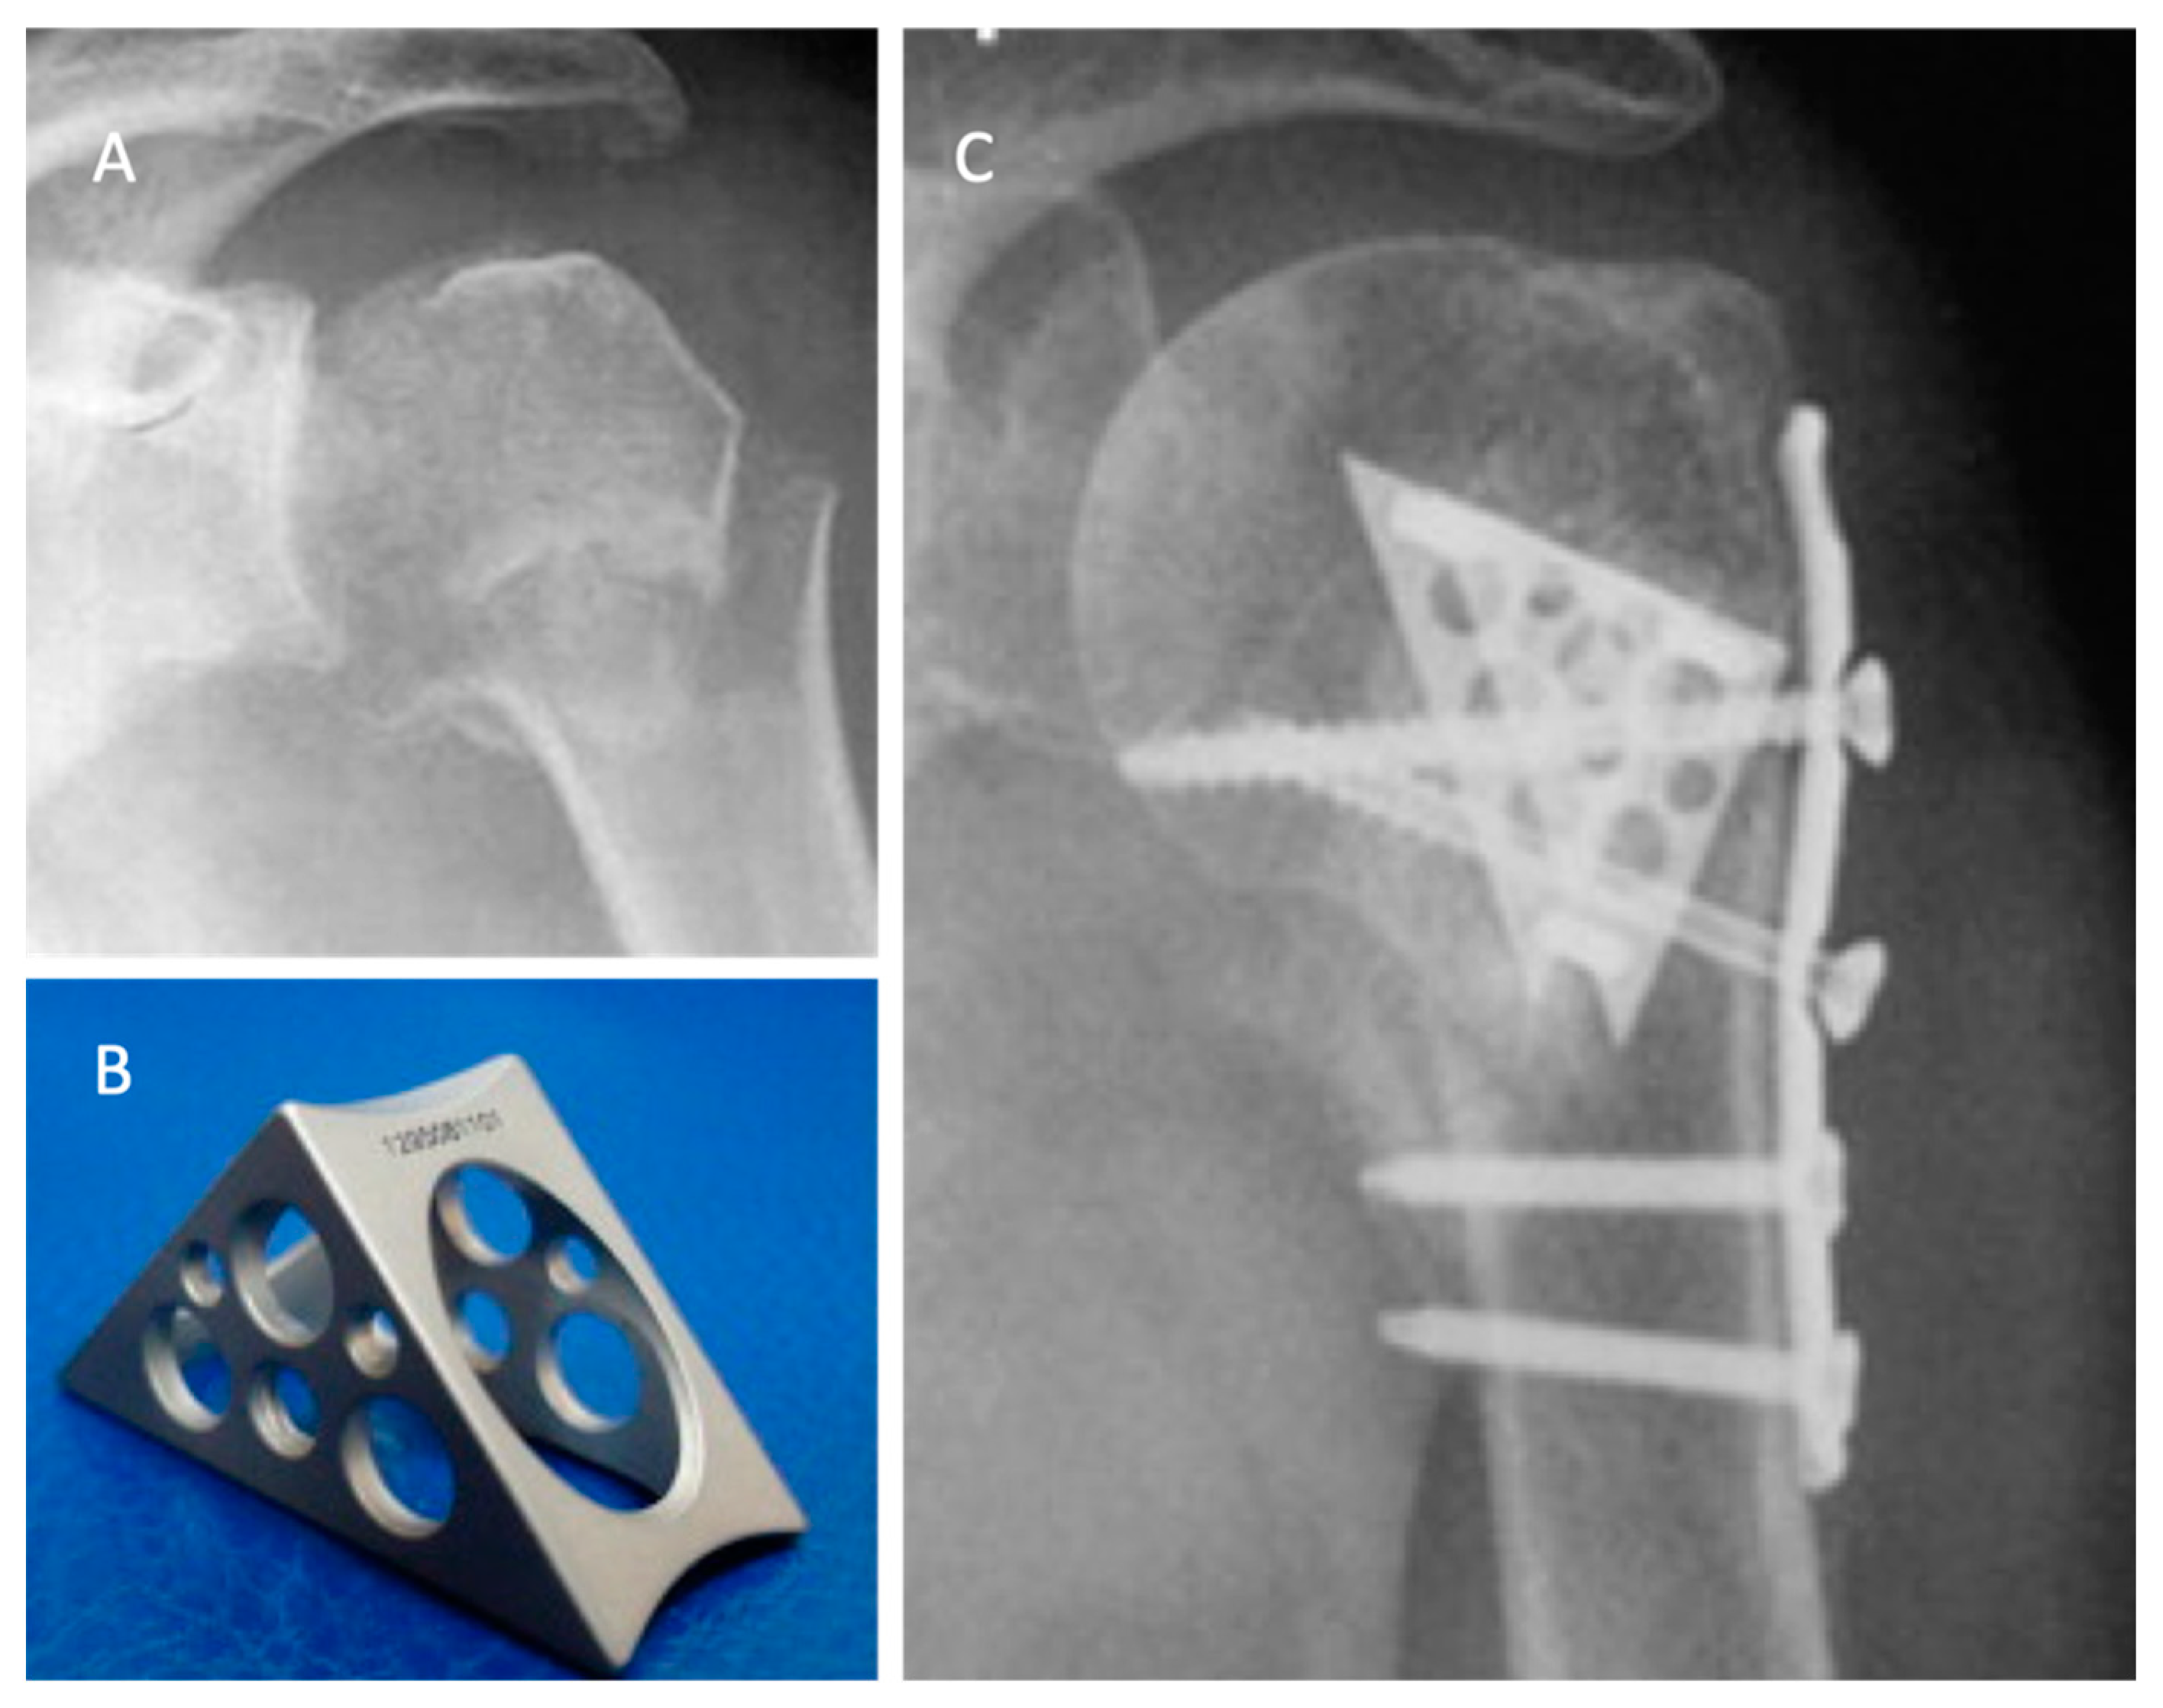

In 2018, Katthagen et al. [30] prospectively treated 24 proximal humeral fractures with the PHILOS plate (DepuySynthes, West Chester, PA, USA) and additional humeral head screw augmentation with PMMA (Figure 2).

Figure 2. Postoperative radiographs of an 87-year-old female patient after locked plating of a proximal humeral fracture with additional cement augmentation of the anterosuperior and inferior humeral head screws: (a) anteroposterior view; (b) axillary view. Credit: Figure 3 from Kattaghen et al. [30] http://creativecommons.org/licenses/by/4.0/.

At the follow-up, no screw penetration was reported. The authors compared the results of 24 fractures derived from a historic retrospective cohort of patients, matched for gender, sex, and type of fracture, who received the conventional PHILOS plate without cementation. In the non-augmented group, four patients (16.6%) suffered screw penetration after the first 6 months, with a significantly increased risk of early loss of reduction (p = 0.037). In the augmented group, no implant-related complications were observed, but two patients (8%) had major biological complications (one avascular necrosis of the humeral head and one nonunion). After 12 months, the mean constant score was 72.9 ± 18.1 points in the PMMA-augmented group and 73.0 ± 13.1 points in the non-augmented group (0.557), with no significant differences observed (p = 0.62).